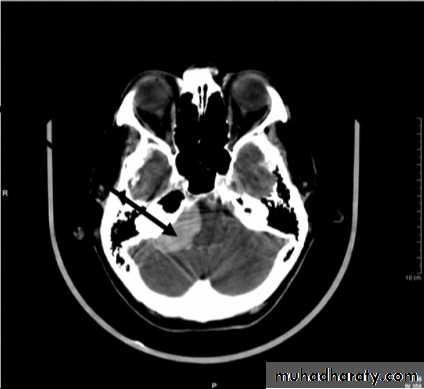

• Computed Tomography scan (CT scan) with/without contrast• Magnetic Resonance Imaging (MRI) with/without contrast